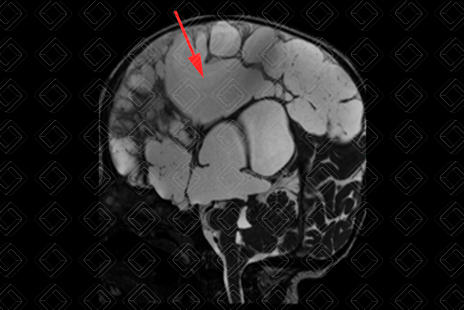

Texto alternativo para a imagem Figura 3. Créditos: Dra. Elazir Mota - Rio de Janeiro/RJ

Descrição das figuras 1, 2 e 3: Ressonância magnética de crânio com sequência CISS. Uma sequência ponderada em T2, cujas imagens císticas apresentam sinal elevado (seta vermelha) e imagens ponderadas em T1 nos planos axial e sagital. É possível observar as múltiplas imagens císticas ocupando a região cortical e de substância branca, predominando no compartimento supratentorial e poupando cerebelo e tronco (setas amarelas).

• Múltiplas cavidades císticas, de tamanhos variados, envolvendo substância branca e região córtico-subcortical;

• Em geral, os cistos poupam cerebelo e o tronco cerebral (exceção para os casos em que ocorre degeneração do trato córtico-espinhal associada);